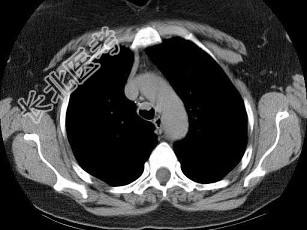

- 单项选择题男,68岁, 呼吸困难、轻度吞咽困难3月余,结合CT图像, 最可能的诊断是 ( )

A、气管乳头状瘤

B、气管脓肿

C、气管炎性假瘤

D、食管癌

E、甲状腺癌